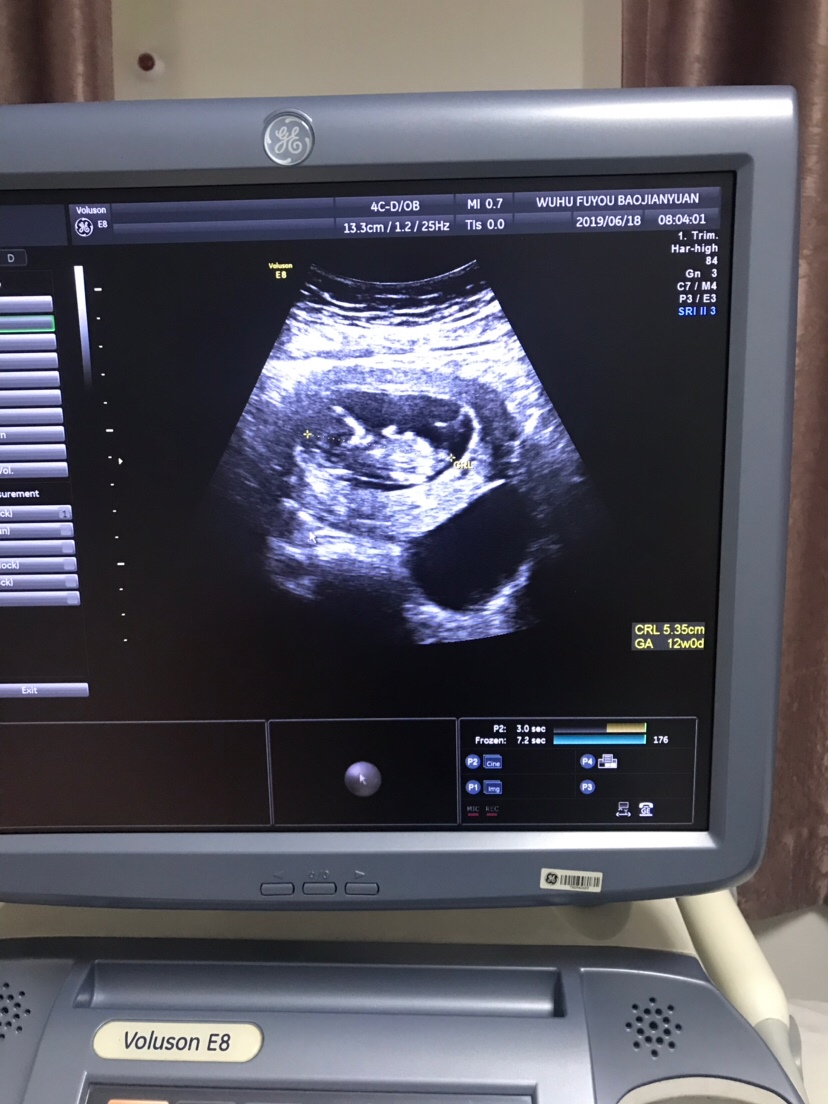

孕8周+3天

我猜是女孩